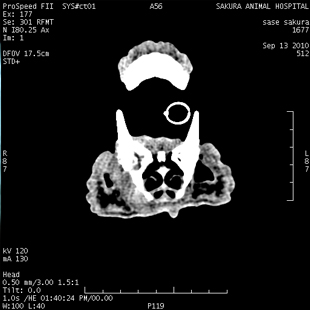

上顎切除 ーその他ー

手術症例紹介